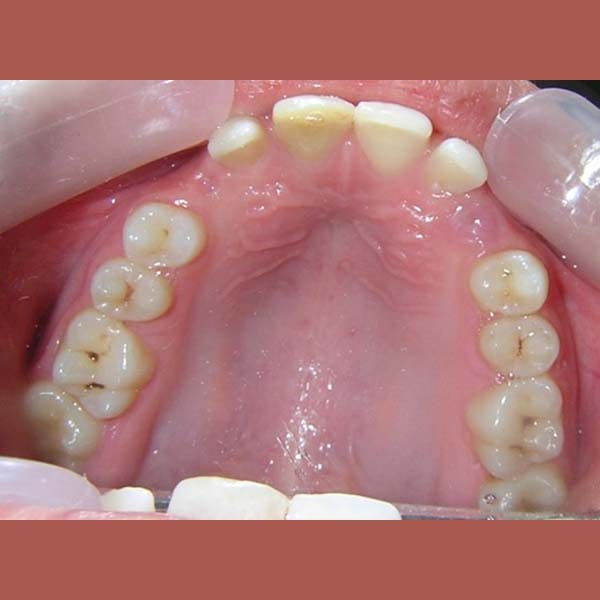

BEFORE

كانت المشكلة الرئيسية في هذه الحالة هي وجود ناب علوي منطمر بالكامل في عظم الفك، وغير قادر على البزوغ بشكل طبيعي.